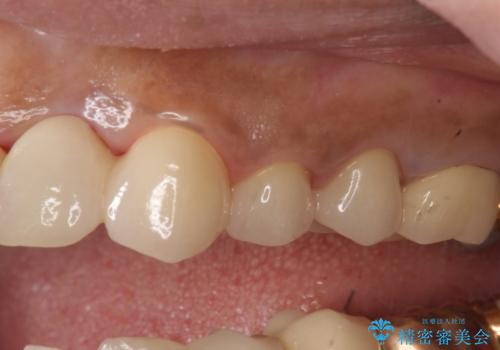

- 左上2番目の歯がグラグラするので診て欲しいといらっしゃった方の症例です。

左上2番目の歯は歯根が破折してため抜歯し、左上123のブリッジによる欠損補綴を行いました。

左上4、5番目の歯は根尖病変を認めたため再根管治療を行い、オールセラミッククラウンによる補綴を行いました。

なお左上4に関しては縁下歯質を改善するため、歯冠挺出を行っております。